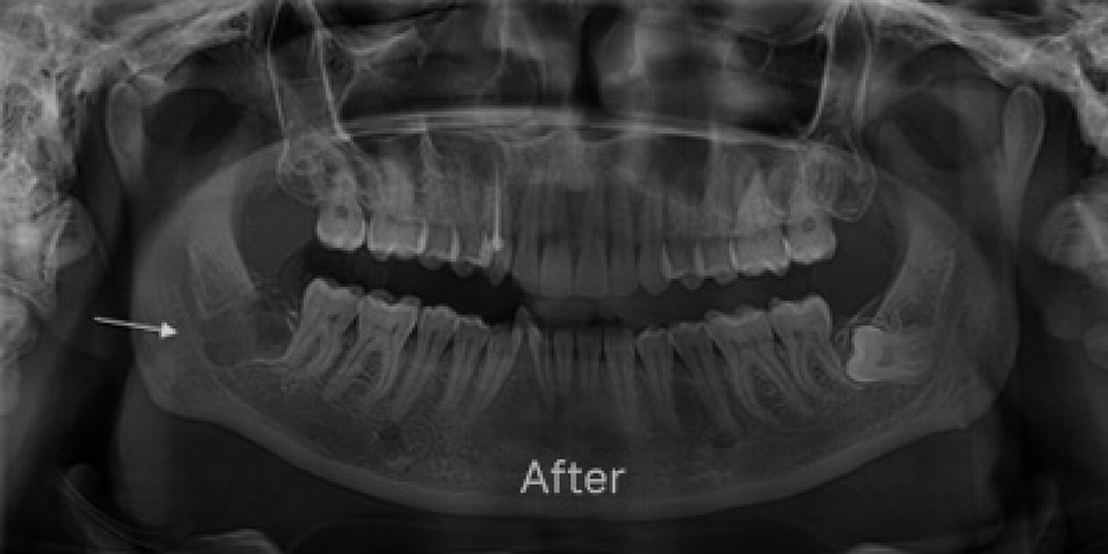

Wisdom Tooth Removal

Whether you need a dental filling Dubai treatment for decay or a dental gap filling to improve aesthetics and bite alignment, our gentle, expert approach protects your teeth and relieves discomfort. We also provide care for wisdom teeth, including safe and effective wisdom tooth extraction Dubai when needed. Count on us to keep your smile healthy, resilient, and looking its best for years to come.

As part of the best wisdom tooth extraction Dubai options, it ensures optimal care, comfort, and long-term oral health.